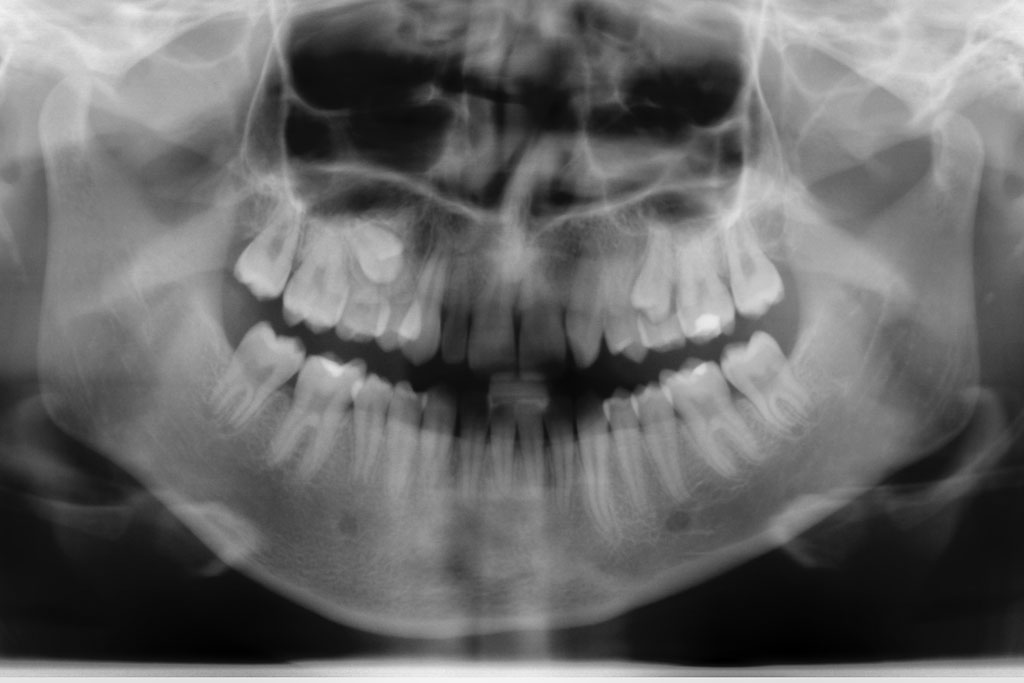

Die Nichtanlage der seitlichen oberen Schneidezähne und der zweiten unteren kleinen Backenzähne (Prämolaren) ist relativ häufig.